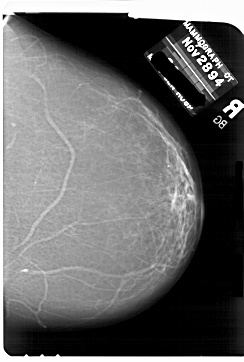

A_1769_1.LEFT_MLO

LEFT_MLO LINES 6706 PIXELS_PER_LINE 5236 BITS_PER_PIXEL 12 RESOLUTION 43.5 OVERLAY